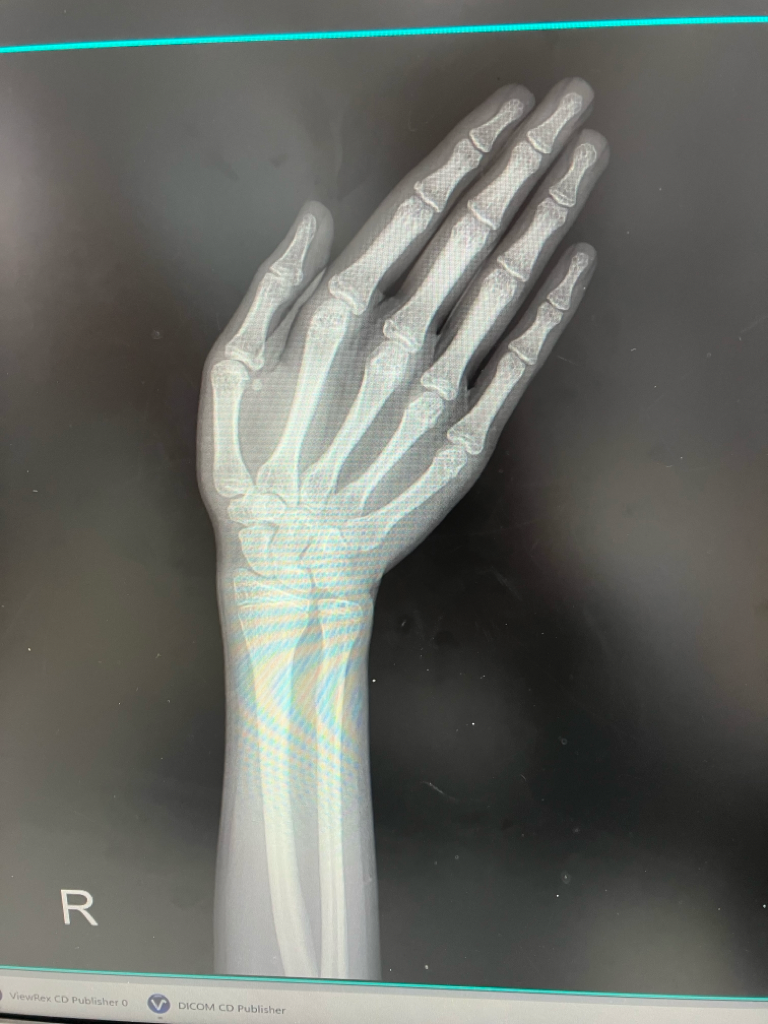

오른쪽 엑스레이, 뼈나이 몇 살로 보이나요?

오른손이기도 하고 흐리기도 하지만 성장판이 대충 닫혀가는 것 같아서 여쭤봐요. 여아이고 2010년 8월생입니다.......